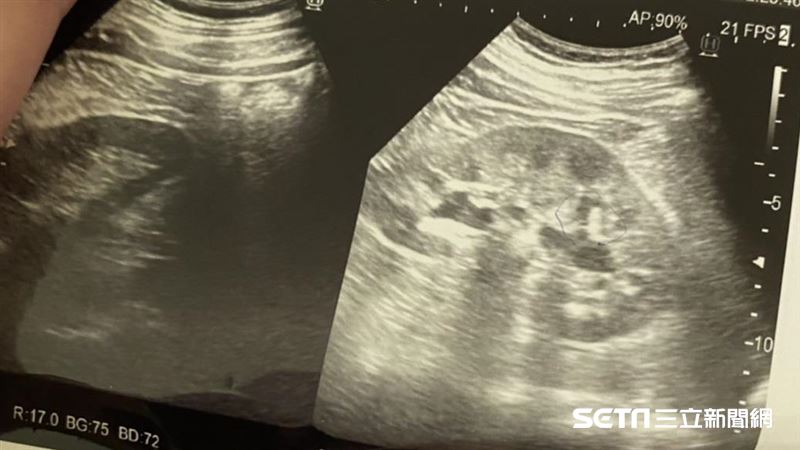

腎結石通常是尿液中某些物質過度濃縮的結果。當草酸、鈣、尿酸等成分的濃度超過尿液的溶解極限時,這些物質會逐漸沉積形成結晶,長時間累積後便形成結石。其中,草酸鈣結石最為常見,約占所有腎結石的七成以上。由於初期結石體積小且症狀不明顯,許多人直到結石卡住尿路,疼痛難忍時,才驚覺自己早已是高風險族群。